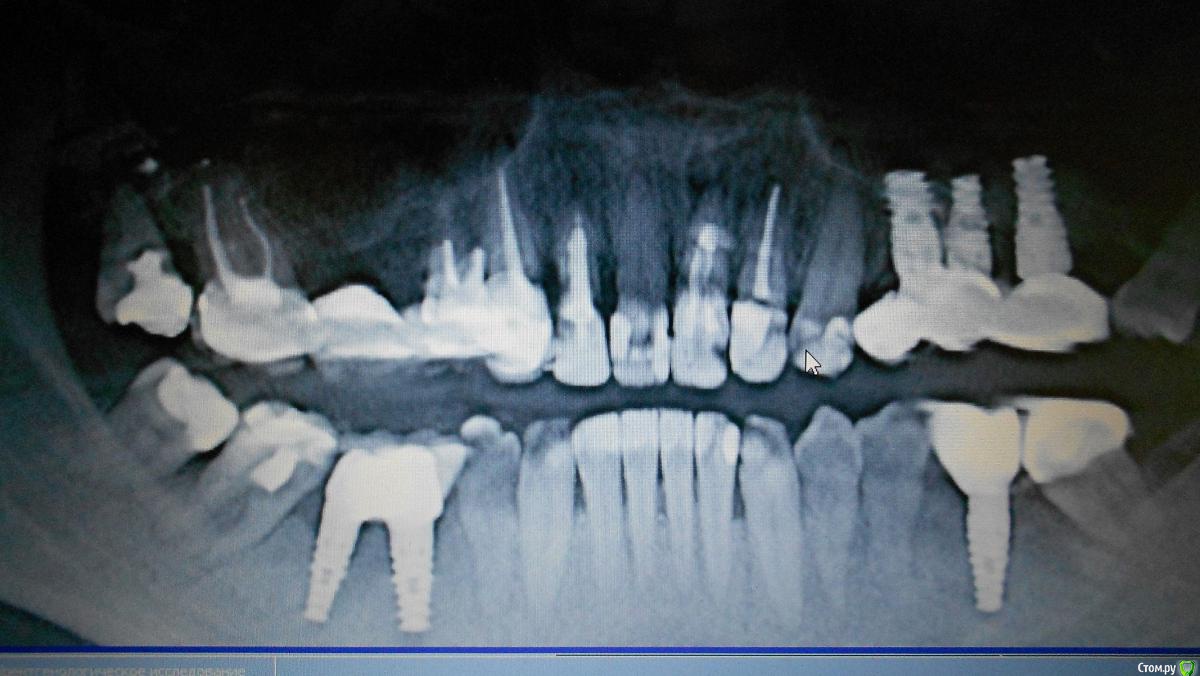

Oks72 Опубликовано 22 февраля, 2018 Автор Поделиться Опубликовано 22 февраля, 2018 (изменено) Добавила снимки. Изменено 22 февраля, 2018 пользователем Oks72 Ссылка на комментарий

Bier Опубликовано 22 февраля, 2018 Поделиться Опубликовано 22 февраля, 2018 если эстетически работа вас не устраивает, то необходимо удалить ближний имплантат, потом поставить в более выгодную позицию. Ссылка на комментарий